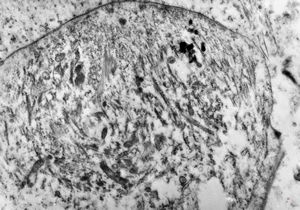

M,56y. | amyloidosis - tendon